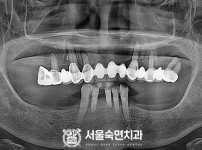

임플란트-전후사진4